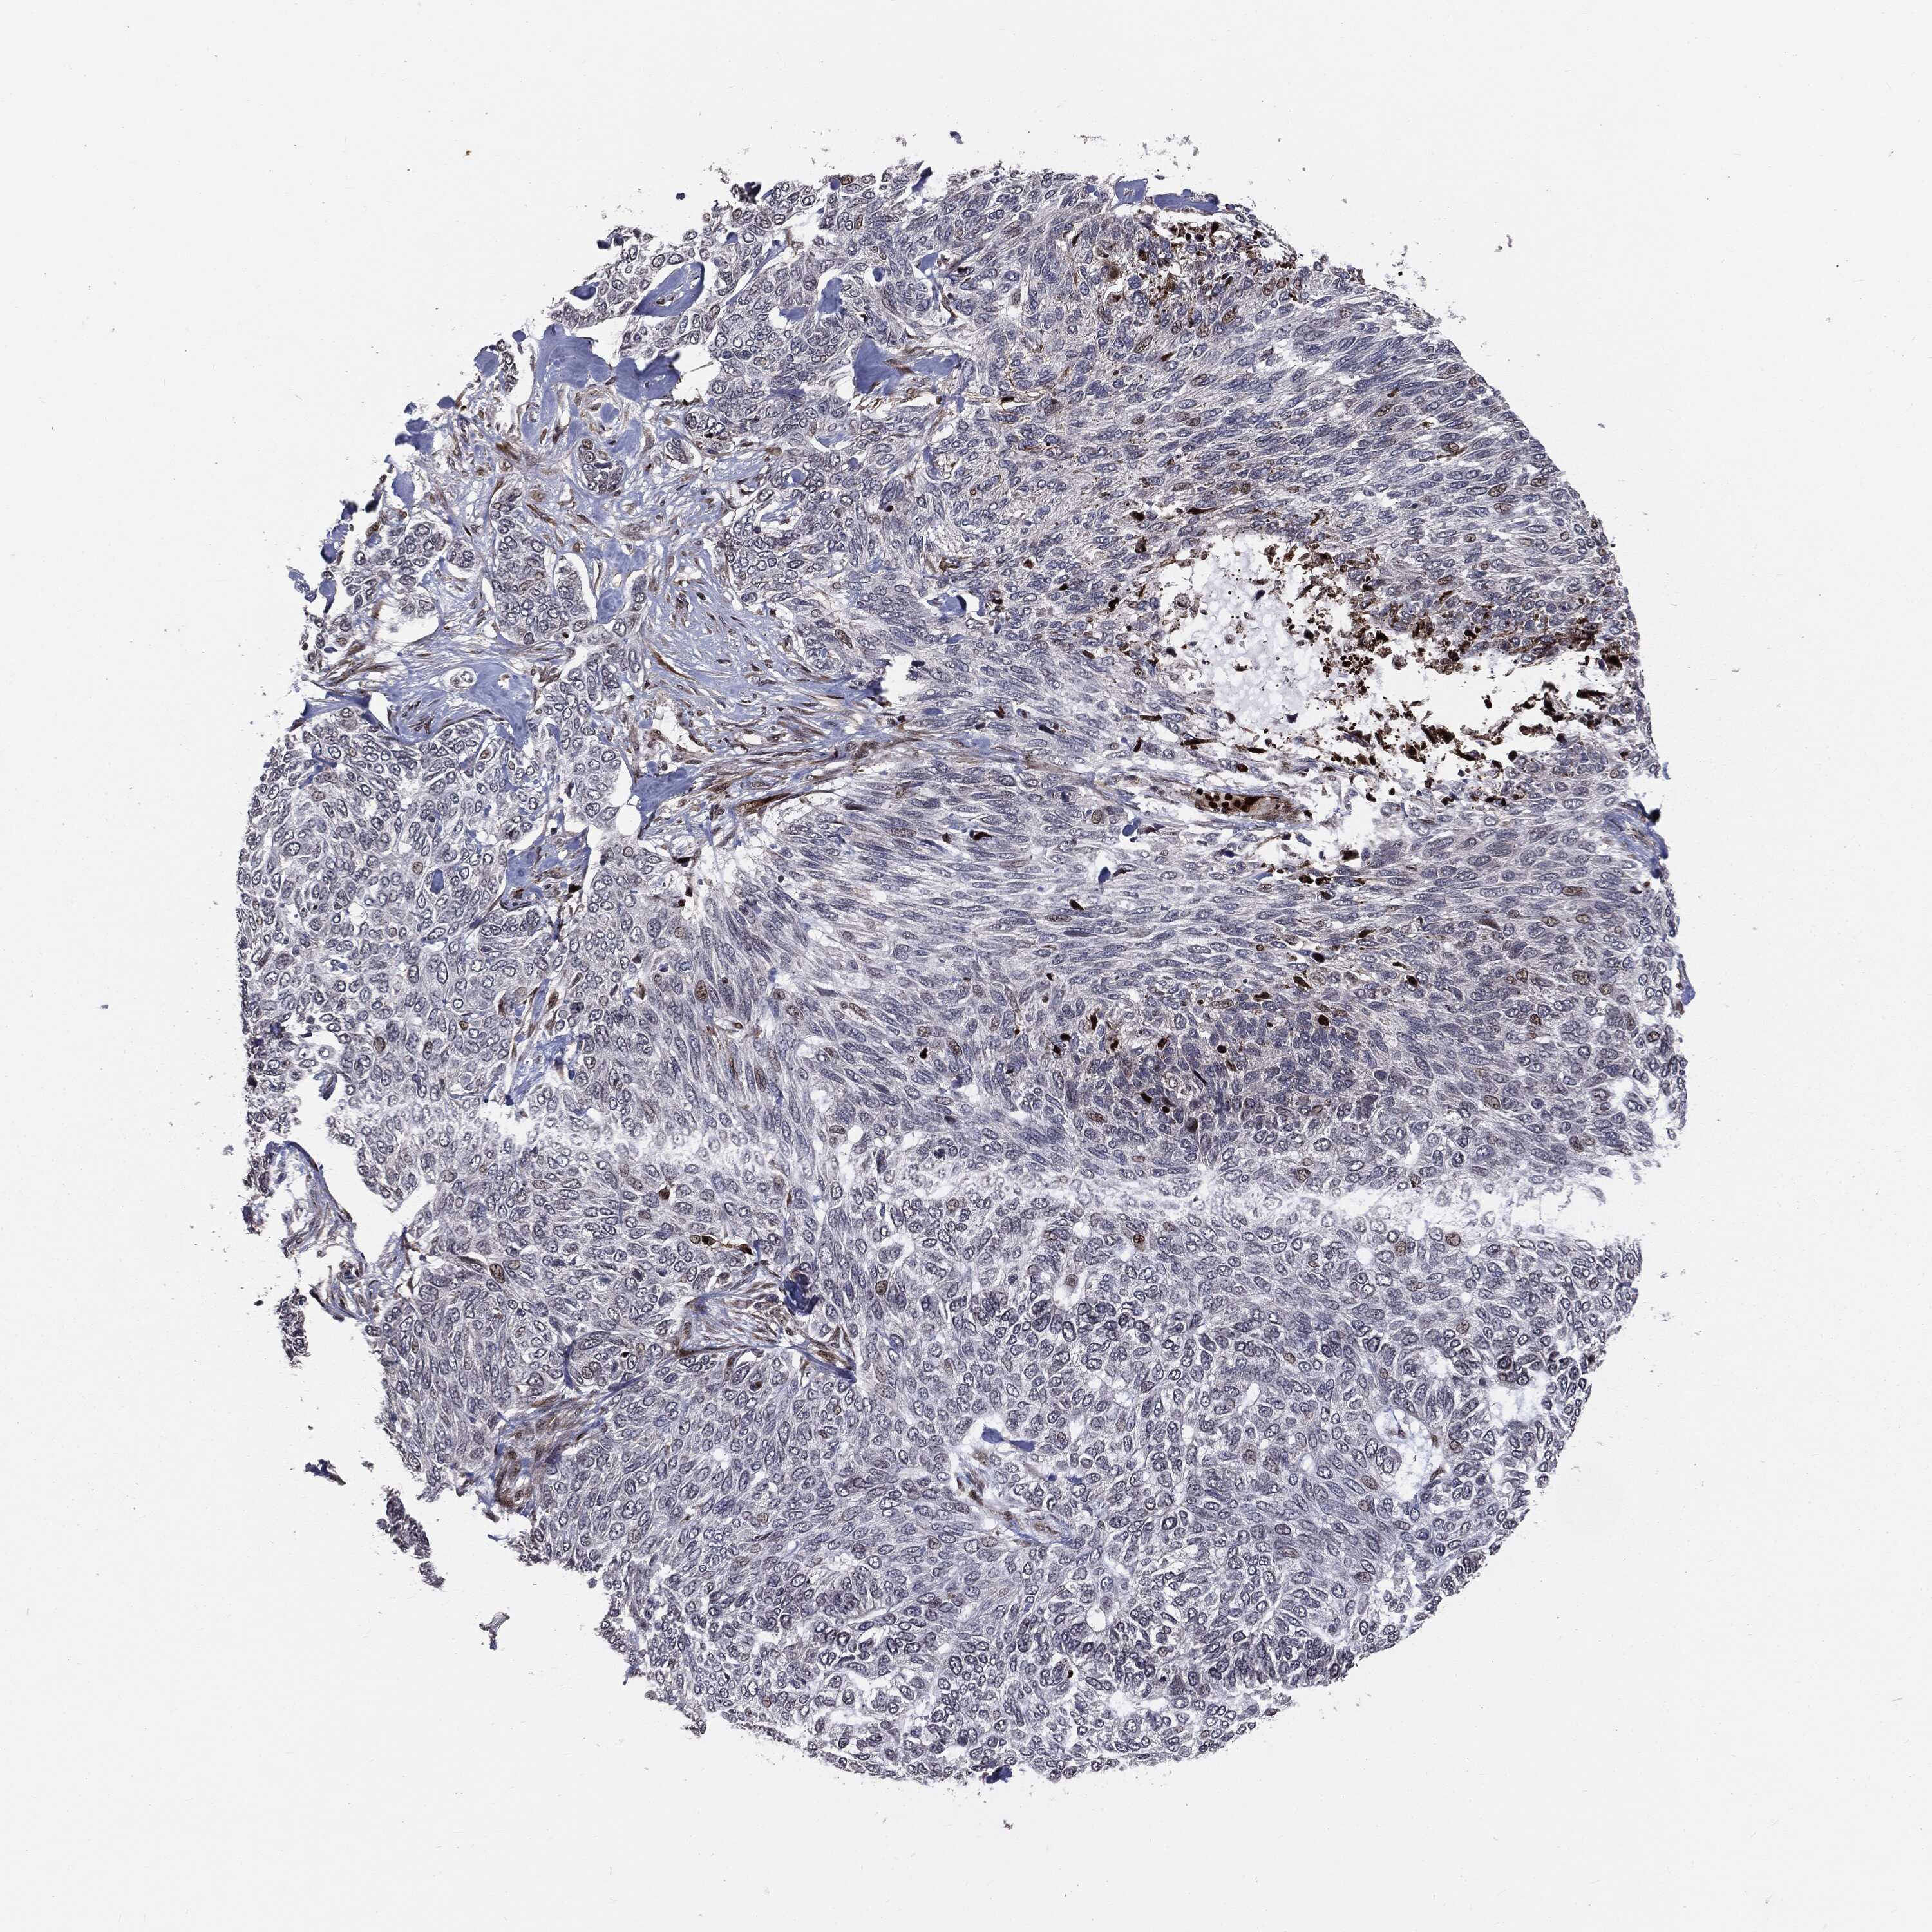

SKIN CANCER - Protein expressioni

A mouse-over function shows sample information and annotation data. Click on an image to view it in a full screen mode. Samples can be filtered based on level of antibody staining by selecting one or several of the following categories: high, medium, low and not detected. The assay and annotation is described here.

Antibody stainingi

Antibody staining in the annotated cell types in the current human tissue is reported as not detected, low, medium, or high, based on conventional immunohistochemistry profiling in selected tissues. This score is based on the combination of the staining intensity and fraction of stained cells.

Each image is clickable and will lead to virtual microscopy that enables deeper exploration of all samples and also displays staining intensity scores, fraction scores and subcellular localization as well as patient and tissue information for each sample.

Antibody HPA019154

Squamous cell carcinoma in situ, NOS